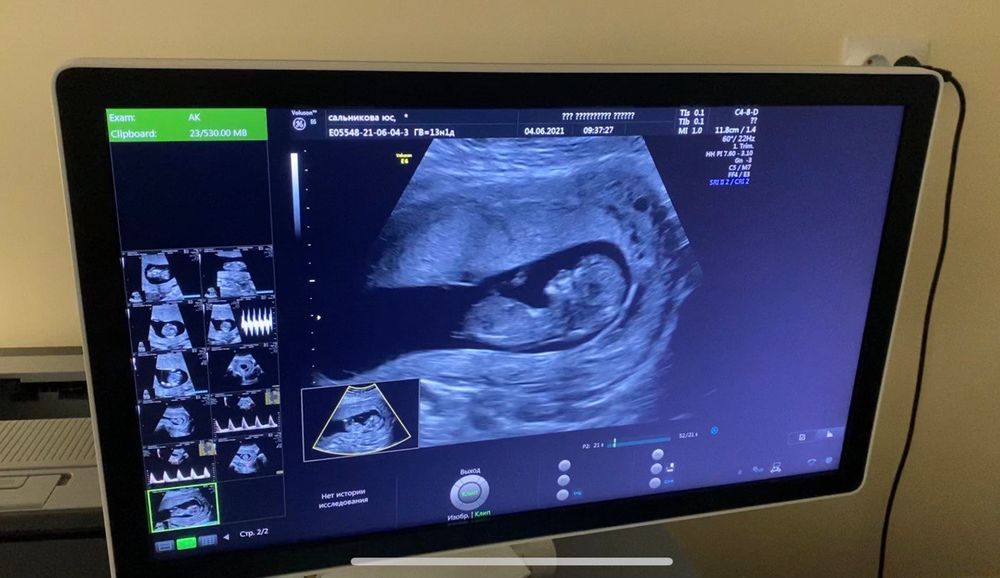

Итоги первого скрининга

Бэйбик само очарование💞! Насчёт пола ребенка, тут конечно практически не видно полового бугорка, но если то что я увидела и есть он, то могу предложить в процентном соотношении 89%, что это девчуня 💝💓💖! Тут ещё помимо бугорка, по черепу гладкому, без сильной выпуклости думаю, что в животике гостит наследница 💞💗😻! Главное от всего сердца желаю вам удачной беременности и родов в срок, и конечно же, чтобы родился здоровеньким 💓🙏🏻✊🏻

Бугорок её вижу, но интуитивно парень мне кажется

На мальчика похоже

Мальчик!

Девочка!!!!